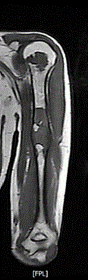

Osteofibröz displazi Campanacci hastalığı; nadir bir hastalıktır, tibia (kaval kemiği) ve fibulayı tutar. Özellikle tibianın 1/3 orta kısmında görülür. Tibia öne ve yana doğru eğilir. Kırık gelişmediği sürece ağrı olmaz. Patolojik kırk konservatif olarak tedavi edilir. Deformiteyidüzeltmek ya da deformite gelişmesini önlemek amacı ile cerrahi olarak tedavi edilir.